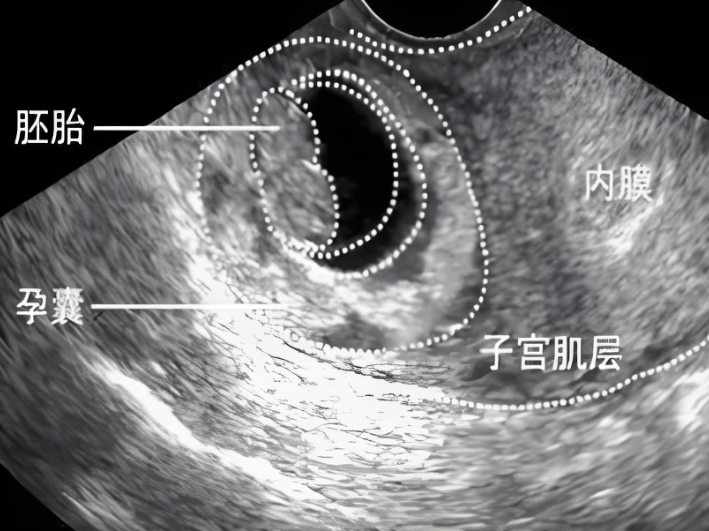

怀孕后,子宫内可见孕囊。若孕囊内没有胚胎组织、胎芽或胎心搏动现象,则意味着妊娠失败。女性往往需要接受清宫手术,将未发育的孕囊从子宫内清除。这不仅会对女性的子宫内膜造成直接损伤,增加后续受孕的难度,还可能引发诸如感染、出血等并发症,严重威胁女性的生殖健康。

正常的子宫内膜厚度在排卵期一般为8-12毫米,这样的厚度能够为胚胎着床提供适宜的条件。如果子宫内膜厚度不足6毫米,胚胎就很难成功扎根,即便着床后,由于无法从子宫内膜获取足够的营养支持,也容易发育异常,导致空囊。